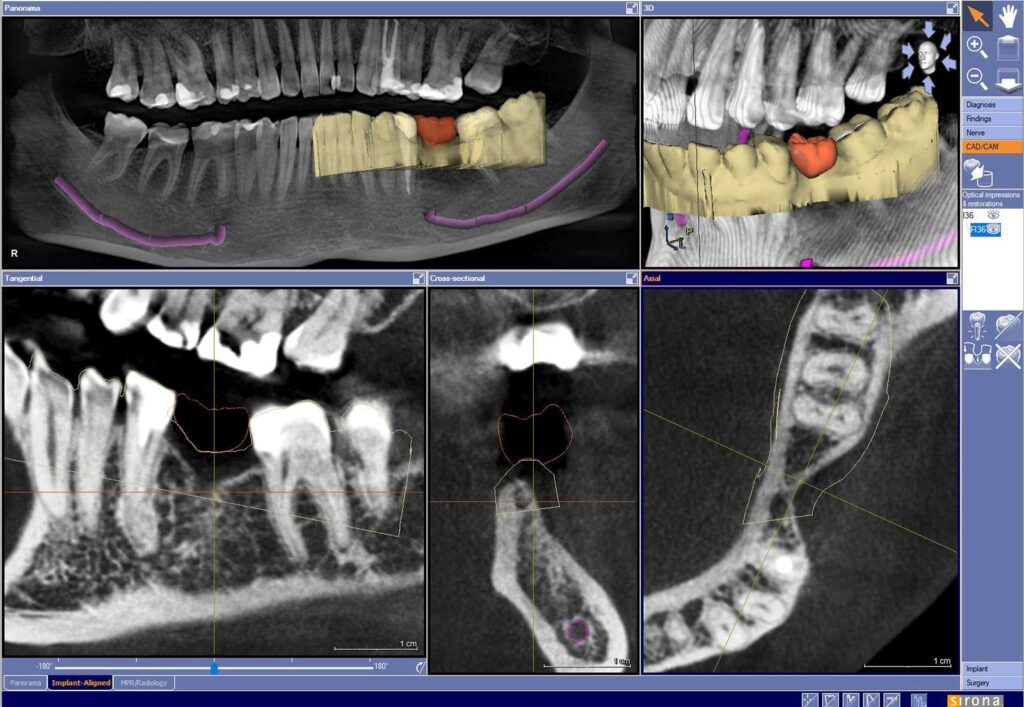

Podczas zabiegów implantacyjnych wykorzystujemy szablony chirurgiczne – komputerowo nawigowana implantologia.

Zadaniem szablonów jest precyzyjne prowadzenie narzędzi chirurgicznych w określonym miejscu i pod określonym kątem. Narzędzia przygotowywane są na podstawie planu przedoperacyjnego. Każdy szablon jest niepowtarzalny i pasuje tylko do jednego pacjenta.

Zalety wykorzystania szablonów podczas nawigowanej implantologii to między innymi:

– znaczne skrócenie zabiegu,

– umiejscowienie implantu w kości z dokładnością do dziesiątych części milimetra,

– możliwość jednoczasowego osadzenia odbudowy protetycznej,

– brak „cięć” w jamie ustnej w celu uwidocznienia miejsca implantacji.